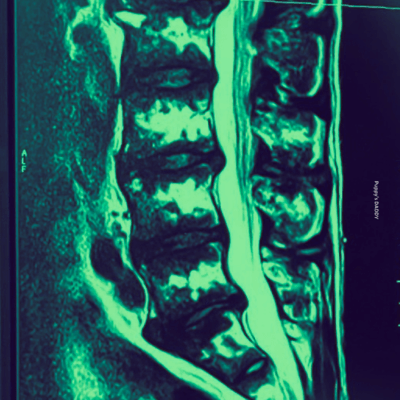

愛があっても会えない

AIになって会いたいね